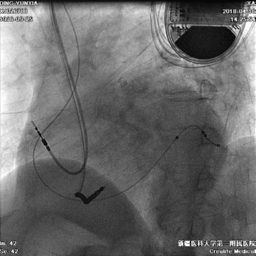

电极植入

● 延PTCA导丝送入电极至远端。

● 植入心房电极和右室除颤电极,连接起搏器。